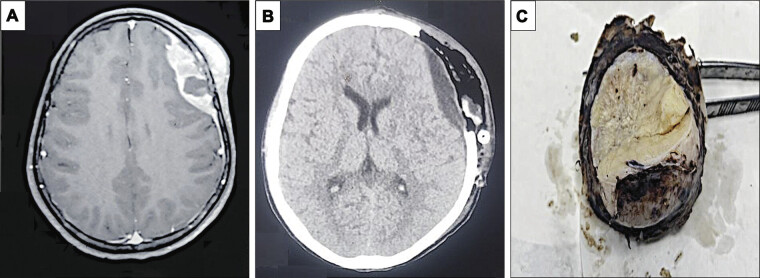

尤文氏肉瘤虽然罕见,但主要影响儿童和年轻人,通常表现在长骨上。颅脑受累,特别是在额骨,是非常罕见的,提出诊断和治疗的挑战。细致的病理评估是识别和处理这种非典型表现的关键。一名16岁男性表现为左额叶肿胀和神经系统症状。影像学显示左额骨占位性病变伴颅内延伸。组织病理学根据特征性发现和阳性免疫组织化学标记证实为尤文氏肉瘤。鉴别诊断包括转移性神经母细胞瘤、原始神经外胚层肿瘤和脊索瘤,强调综合评估的重要性。尤文氏肉瘤累及颅骨需要多学科的方法来准确诊断和治疗。本病例强调了临床、放射学和病理评估在识别罕见表现中的重要性。团队之间的协作对于定制管理策略和最佳患者结果至关重要。

Ewing's sarcoma, though rare, primarily affects children and young adults, commonly manifesting in long bones. Cranial involvement, particularly in the frontal bone, is exceptionally uncommon, posing diagnostic and therapeutic challenges. Meticulous pathological assessment is crucial for recognizing and managing such atypical presentations. A 16-year-old male presented with left frontal swelling and neurological symptoms. Imaging revealed a space-occupying lesion involving the left frontal bone with intracranial extension. Histopathology confirmed Ewing's sarcoma based on characteristic findings and positive immunohistochemical markers. Differential diagnoses include metastatic neuroblastoma, primitive neuroectodermal tumors, and chordomas, highlighting the importance of comprehensive evaluation. Ewing's sarcoma involving the skull necessitates a multidisciplinary approach for accurate diagnosis and management. This case underscores the significance of clinical, radiological, and pathological assessments in recognizing rare manifestations. Collaboration among teams is crucial for tailored management strategies and optimal patient outcomes.